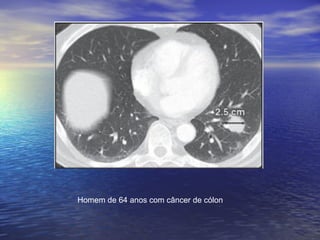

Homem de 64 anos com câncer de cólon